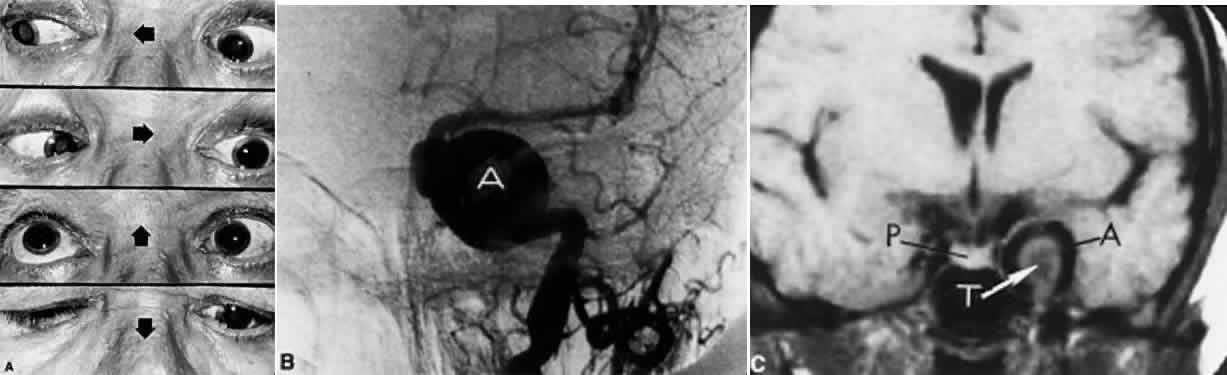

FASCICULAR LESIONS Deficits of the oculomotor fasciculus are usually identified by the accompanying brain stem signs. Oculomotor palsy with contralateral hemiplegia (Weber syndrome) indicates involvement of the corticospinal tracts. Contralateral ataxia and intention tremor (Benedikt syndrome) indicates involvement of the red nucleus (see Fig. 2). Nothnagel syndrome is an eponym given when signs of both Weber and Benedikt syndromes are present. Midbrain vascular accidents account for most fascicular defects. Ksiazek84 shed some light on the fascicular arrangement of the oculomotor nerve based on two patients with partial oculomotor paresis, each with pupillary mydriasis, significant inferior rectus paresis, and medial rectus paresis. Neuroimaging revealed a lesion in the fascicular portion of the nerve, thus indicating the proximity of these fibers in the fasciculus. Monocular elevator paresis (superior rectus and inferior oblique) in mass compression of the oculomotor fasciculus has also been reported.85 In this regard, Castro and associates86 proposed the mediolateral somatotopy of the oculomotor fascicular fibers within the mesencephalon with the inferior oblique and superior rectus muscles being most lateral, and the pupilloconstrictor fibers and inferior rectus being most medial. The levator palpebrae fascicles are in an intermediate location between the superior rectus and medial rectus fascicles. INTERPEDUNCULAR LESIONS Basal lesions, including the rare rostral basilar artery aneurysm, may encroach on the oculomotor nerves as they exit in the interpeduncular space. Such slow-growing aneurysms, either saccular or fusiform, may present as partial oculomotor palsies with or without involvement of pyramidal tracts, and without subarachnoid hemorrhage.87 Aneurysms of the posterior communicating artery, on the other hand, are probably the most common lesions causing acute spontaneous oculomotor palsies (Fig. 12). According to Hyland and Barnett,88 the oculomotor palsy that occurs with posterior communicating aneurysm is not necessarily due to mass effect per se, but rather is attributed to hemorrhage that suddenly enlarges the aneurysmal sac to which the oculomotor nerve is adherent, or to hemorrhage into the substance of the nerve itself. Most patients present, therefore, with an intensely painful, complete unilateral oculomotor palsy in association with other signs and symptoms of subarachnoid hemorrhage. Few patients with symptomatic posterior communicating aneurysms are found in office waiting rooms: they are usually obtunded or comatose in emergency rooms. Involvement of pupillary fibers is such a consistent finding in third nerve palsies due to bleeding aneurysms that most clinicians concur in this useful dictum: a pupil-sparing, but otherwise complete, third nerve palsy is very unlikely to be due to posterior communicating aneurysms. Careful pupil evaluation may disclose subtle abnormalities in “apparent pupil-sparing,” especially in cases of aberrant regeneration or with chronic cavernous sinus lesions. Generally, in patients at least 50 years of age or older, an acute, isolated, painful oculomotor palsy that spares the pupil is caused by intraneural ischemia; nevertheless, these patients must be carefully observed for further evolution. In our opinion, an acute complete oculomotor palsy with moderate to major mydriasis, even when diabetes is present, is an indication for cerebral arteriography. It should be emphasized that magnetic resonance angiography may not detect aneurysms smaller than 3 to 4 mm.89 The clinical management of patients with relative pupil-sparing third nerve palsies remains in debate. Observation alone arguably is appropriate management of such patients; however, since practically every conceivable combination of partial ophthalmoplegia and pupillary abnormality has been reported in aneurysmal compression of the third nerve, it is better to err on the side of caution and perform angiography more frequently. It is incumbent upon the physician to evaluate carefully the proportion of ophthalmoplegia and ptosis in relation to the degree of pupillary abnormality when deciding appropriate workup of these patients. Again, the increasing sensitivity of magnetic resonance angiography has not yet entirely replaced formal angiography. Certainly, neurosurgical intervention requires conventional cerebral arteriography before surgical treatment. Capó and colleagues90 pointed out that the interval from onset to maximal ophthalmoplegia does not differentiate between microvascular (3.3 days) and aneurysm (3 days), but that failure to recover within 4 to 8 weeks requires further evaluation. Other partial oculomotor palsies occur regularly with cavernous sinus masses and parasellar syndromes (see below), accompanied by variable pupillary findings. Furthermore, both acute and chronic lesions may produce incomplete palsy of the superior division (supplying levator palpebrae and superior rectus muscles) or of the inferior division (medial and inferior recti, inferior oblique and pupillomotor fibers). If pain or first trigeminal division numbness are absent, and if the pupil is uninvolved, such fractional oculomotor pareses are regularly misinterpreted as myasthenia or local orbital inflammations. Guy et al91 described five patients with isolated ptosis and elevator paresis in abduction, consistent with selective “superior division” involvement. They also discussed five previously reported cases with the following respective diagnoses: (1) intracavernous aneurysm (usually with associated Horner's syndrome) and basilar artery aneurysm; (2) diabetic ophthalmoplegia; (3) meningitis; (4) dural lymphoma; and (5) postsurgical manipulation of parasellar structures. In essence, there was little anatomic correlation with the physical separation into superior and inferior oculomotor trunks that occurs in the cavernous sinus. Moreover, two patients sustained superior division palsies during surgical manipulation of the subarachnoidal portion of the oculomotor nerve trunk. A number of cases of inferior rectus paresis, isolated or in combination with ipsilateral or contralateral superior rectus paresis, have been construed as focal lesions involving the rostral portion of the oculomotor nuclear complex.80–82 Oculomotor palsy following head trauma is not rare, but probably occurs less frequently than traumatic fourth nerve palsies. As a rule, such closed-head injury causes loss of consciousness and is accompanied by skull fracture, but this is not invariable. Injury to the ocular motor nerves in road accidents was studied by Heinze,92 who dissected the cadavers of 21 fatal cases. He found that the relationship of frontal or temporal fractures to neural damage was unpredictable. In fact, intact nerves were encountered adjacent to gross fracture sites. The oculomotor nerve was damaged at three locations: (1) avulsion of the rootlets at their ventral exit from the brain stem; (2) contusion necrosis of the most proximal portion of the nerve trunk; and (3) intraneural and perineural hemorrhage of the nerve trunks at the level of the superior orbital fissure. Of great interest are Heinze's findings of focal hemorrhages in extraocular muscles, usually associated with fractured orbital bones. Eyster et al93 reported three patients with large basicranial tumors, who presented with oculomotor palsies precipitated by mild blows to the head that were insufficient to cause fracture or loss of consciousness. The oculomotor nerves were encased and stretched by tumor, which apparently rendered these tethered nerves vulnerable when innocent head blows abruptly shifted the brain. The authors pointed out that such atypical presentations of intracranial tumors may further mimic aneurysms, since subarachnoid hemorrhage does occasionally occur with tumors. Neetens94 reported an additional three cases of oculomotor nerve palsies after minor trauma in the presence of basal intracranial tumors; the trochlear nerve was involved in all three cases, and in two cases the oculomotor nerve was partially affected. Walter et al95 reported two instances of minor head trauma resulting in complete third nerve palsies attributed to occult posterior communicating artery aneurysms. We have seen a 45-year-old school teacher who experienced an immediate right abducens palsy when playfully slapped on the back of the head; within weeks, other cranial nerve palsies announced the presence of diffuse meningeal spread of carcinoma. In the United States, basilar meningitis is rare, but was formerly encountered with tuberculosis and syphilis. When the third nerve is involved in such cases, progressive defects are the rule and other cranial nerve palsies are commonly found. Oculomotor palsy may especially occur with meningitides in infants, including instances of viral and bacterial (e.g., Streptococcus pneumoniae, Haemophilus influenzae) infections.96 Oculomotor nerve compression by the proximal segment of the posterior cerebral artery, or by the uncus against the petroclinoid ligament, can be seen with increasing cerebral edema or with an ipsilateral expanding supratentorial mass, and it is often heralded by unilateral pupillary dilation (Hutchinson pupil). Progression rapidly leads to complete ocular motor nerve palsy. Keane97 reviewed the ocular motor signs of tentorial herniation, which include anisocoria and parasympathetic pupillary abnormalities, unilateral or bilateral ptosis, internuclear ophthalmoplegia, vertical gaze paresis, and partial third nerve palsies. CAVERNOUS SINUS LESIONS The oculomotor nerve may be involved by inflammatory disease, tumor, aneurysm, arteriovenous fistula, or thrombosis at the level of the cavernous sinus. The third nerve is usually involved in combination with the fourth, sixth, and ophthalmictrigeminal nerves, and accompanying sympathetic paresis may minimize pupillary dilation. The syndrome of the cavernous sinus, therefore, includes multiple ocular motor nerve palsies and pain or numbness in the first trigeminal division. In practice, lesions involving primarily the superior orbital fissure produce signs and symptoms that, with the possible exception of proptosis, cannot be distinguished from those of the anterior cavernous sinus. In particular, dural carotid cavernous fistulas that drain primarily into the inferior petrosal sinus may cause third nerve pareses without significant orbital congestion.98 Third nerve palsies due to lesions in the cavernous sinus tend to be partial in that all muscles innervated by the oculomotor branches need not be involved. This is especially true of pupillomotor fibers, such that the pupil may be normal or minimally involved. This “pupil- sparing” is offhandedly attributed to the superimposition of sympathetic paresis (Horner syndrome), but appropriate pharmacologic tests rarely substantiate this explanation (see below, Parasellar Syndrome). More likely, slowly expanding masses (e.g., infraclinoid aneurysm, meningioma) functionally spare the pupilloconstrictor fibers in the intracavernous portion of the oculomotor nerve. In addition, the levator, superior, inferior, and medial recti may be involved in unequal degrees, but progressive paresis evolves. (Once again, myasthenia must be suspected in any nonpainful, pupil-sparing, nonproptotic ophthalmoplegia, with or without ptosis.) Cavernous sinus lesions are further discussed below. Primary neurinoma of the oculomotor nerve is a relatively rare lesion that should be considered in children or young adults with insidious third nerve palsy. These may occur in the cavernous or interpeduncular portion of the nerve (Fig. 13).99,100